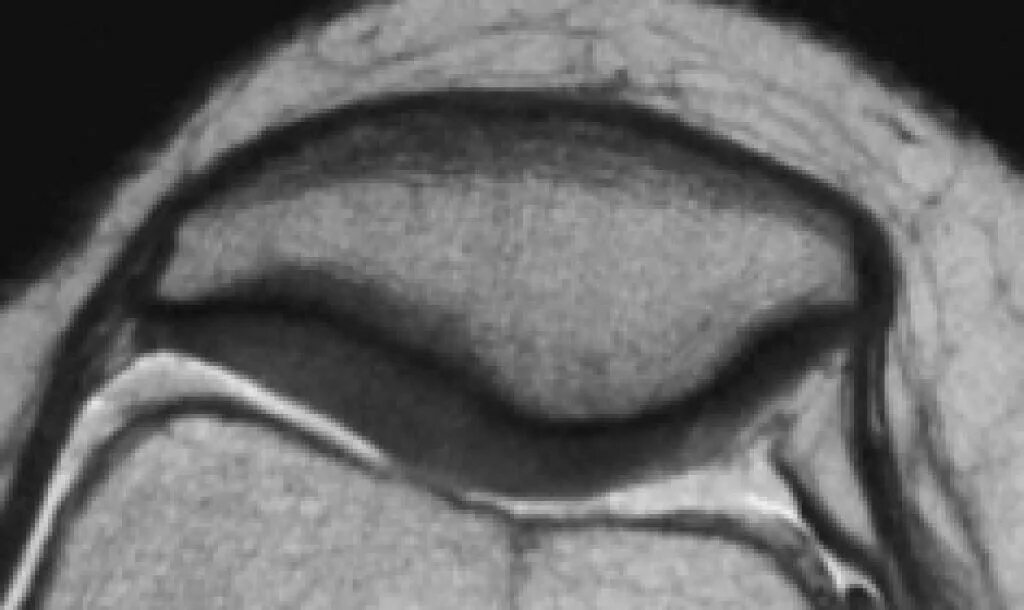

Повреждение хряща по outerbridge